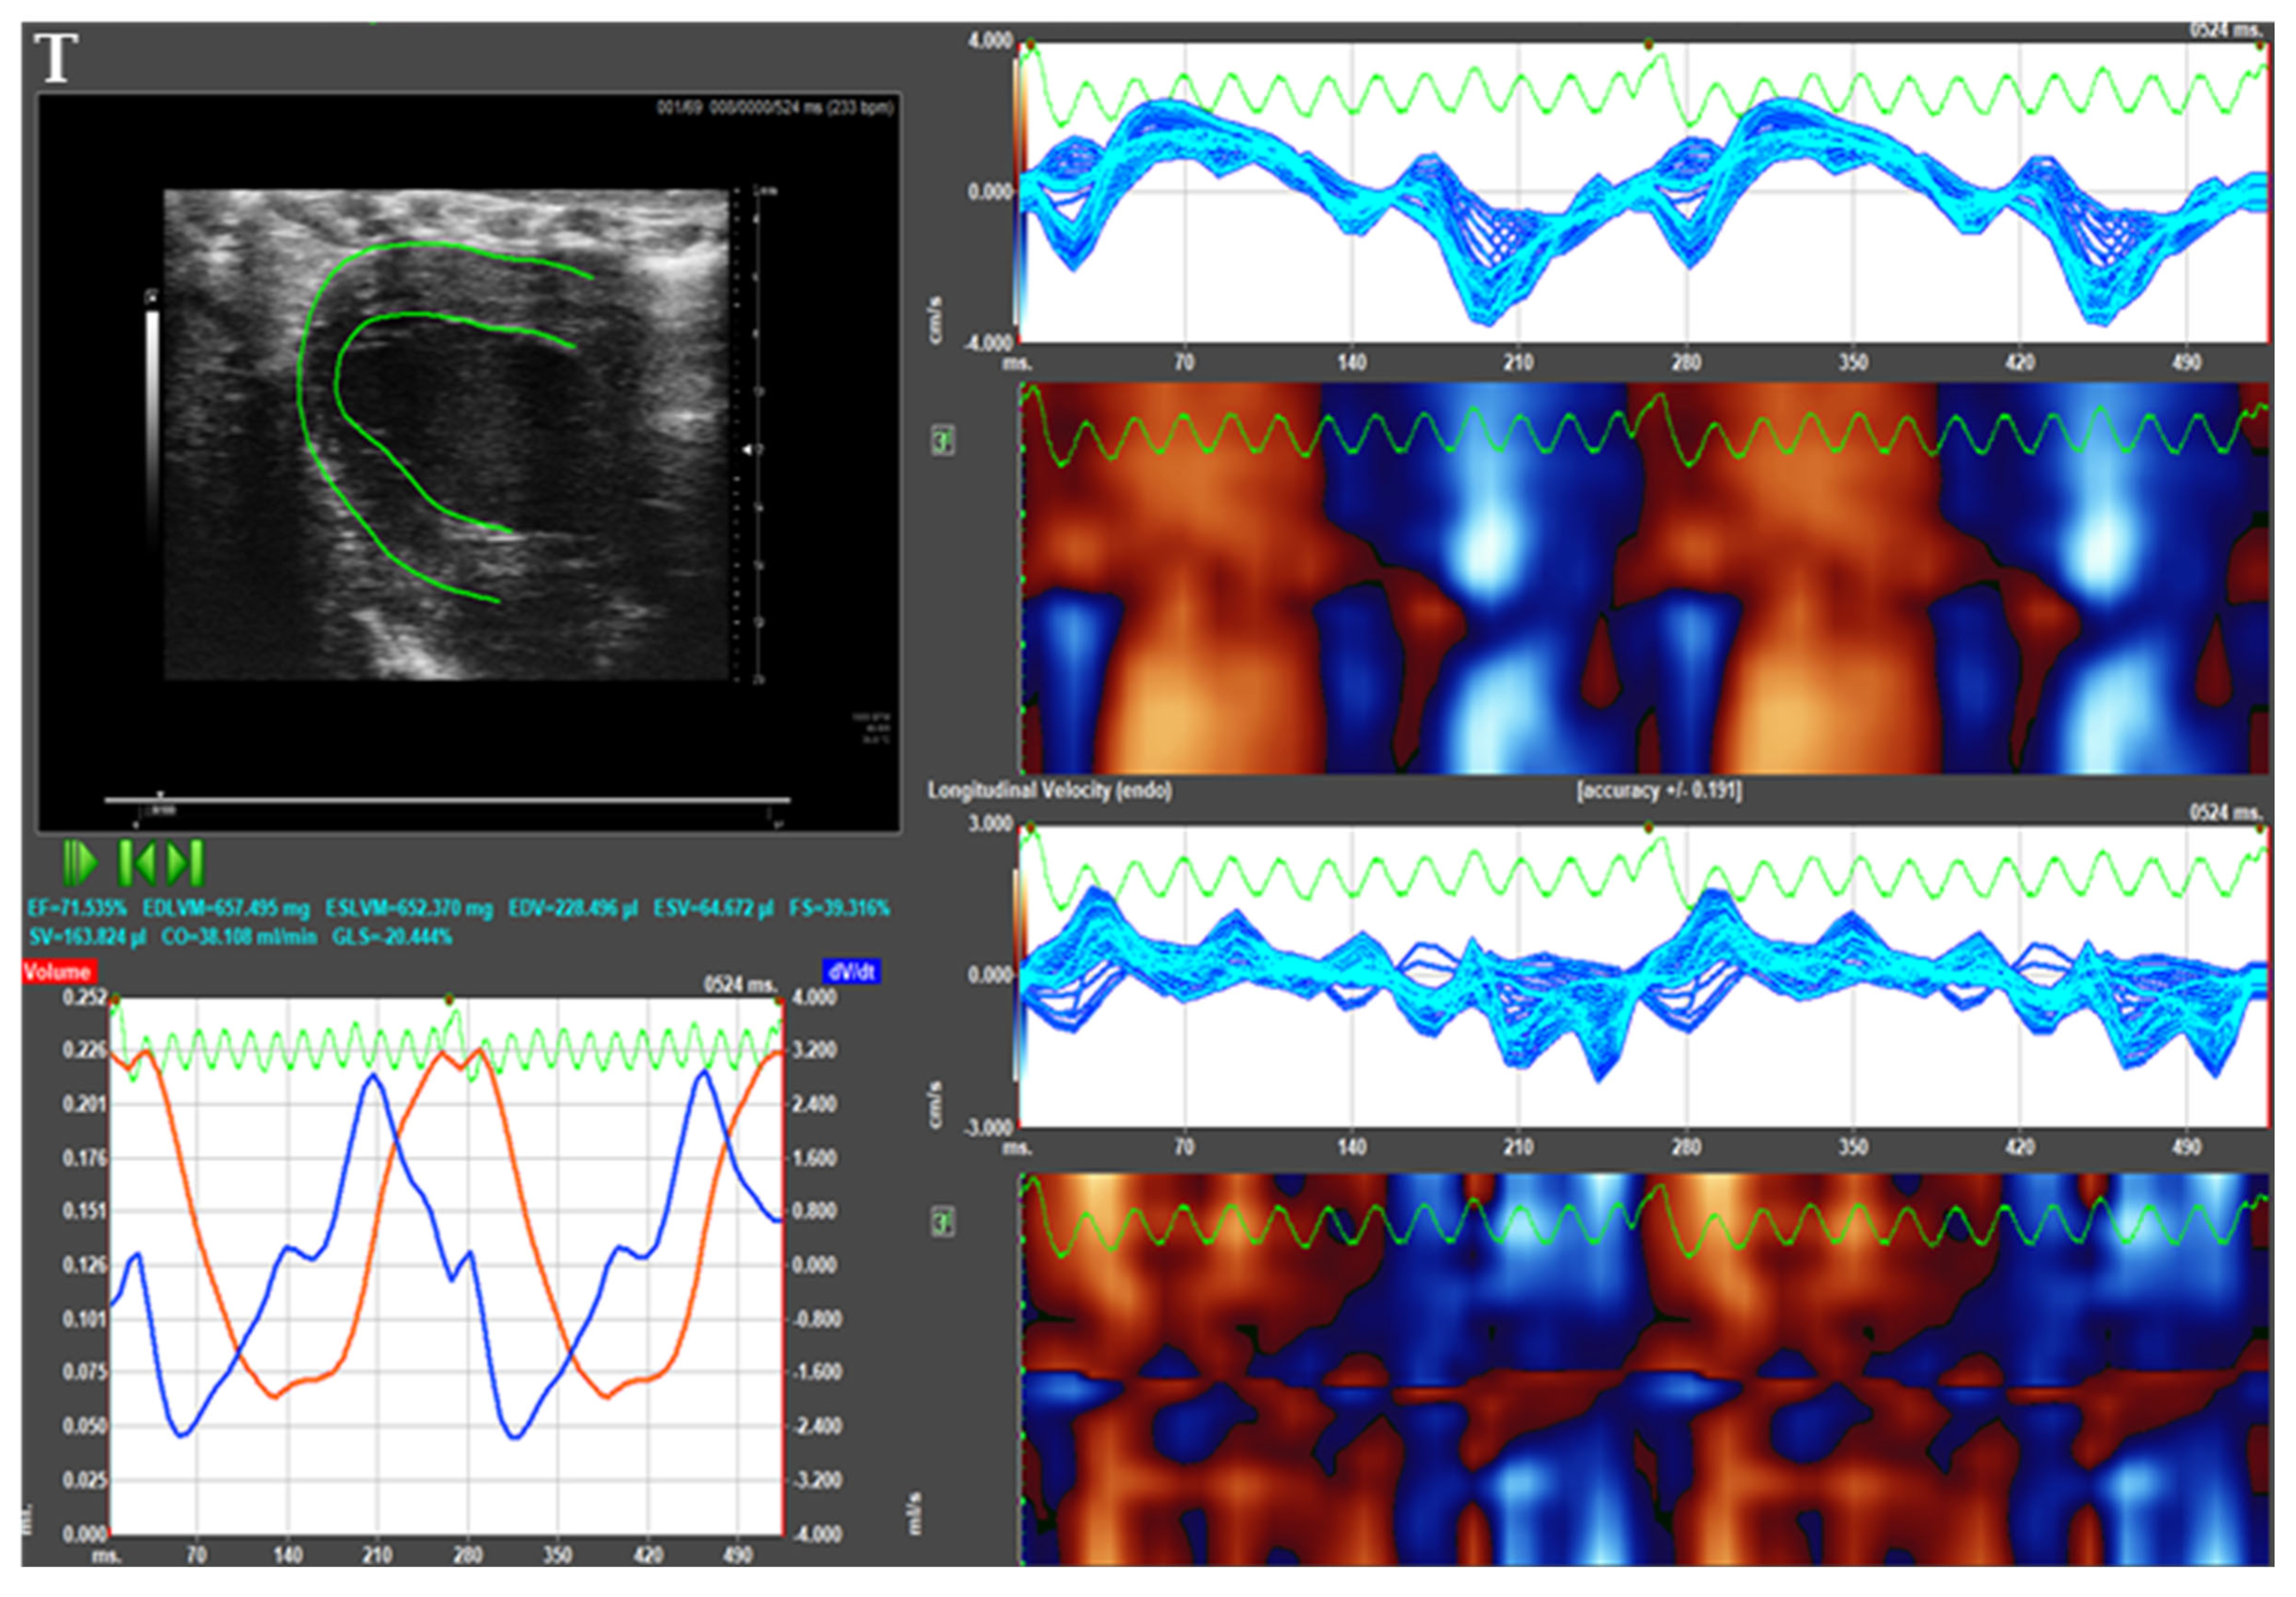

3.3. Echocardiographic Measurements